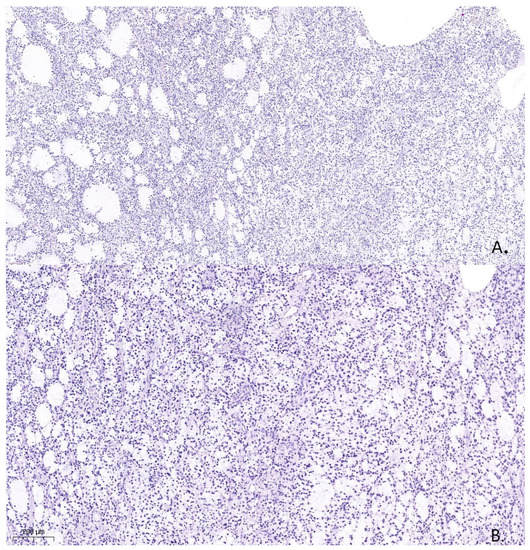

A pathological examination was carried out using an Axioskop 40 microscope by Carl Zeiss (Oberkochen, Germany) and a Pannoramic MIDI scanning microscope, with a total magnification of ×40, ×100, and ×200. The pathological examination with hematoxylin- and eosin-stained slides showed that the tissue was hypercellular, with nuclei that varied in shape and size and had hyperchromatic and polymorphic features (Figure 4). Additionally, the presence of microcysts, glomerular proliferations of vessels, and foci of coagulation necrosis was noted.

Figure 4. Histological specimen from the tumor resection demonstrates Astrocytoma, WHO grade 4, ICD-O code 9445/3. Hematoxylin and eosin. (A). (×100). (B). (×200).